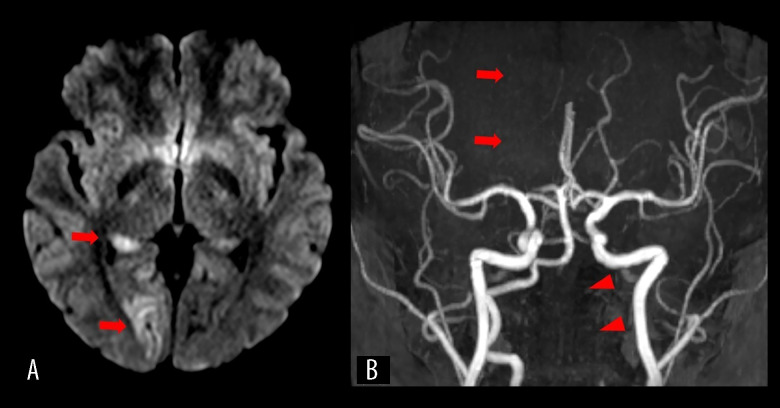

椎动脉夹层(VAD)是青壮年缺血性卒中的重要病因,通常与机械应激源(如创伤、颈部突然运动或剧烈体育活动)有关。虽然电子游戏在传统上并不被认为是一种风险因素,但互动健身游戏的日益流行却引起了人们对其潜在健康影响的关注。病例报告:我们报告了一名25岁的久坐女性,无血管危险因素,她在玩家庭健身视频游戏Ring Fit Adventure(任天堂公司)时,使用基于阻力的控制器进行重复的头顶推拉动作时,出现了急性左侧颈部疼痛。两天后,她突然出现左侧麻木和视觉障碍。神经学检查显示左侧同义性偏视和半感觉缺陷。脑MRI显示右侧枕叶急性梗死,磁共振血管造影显示右侧大脑后动脉闭塞和左侧椎动脉夹层伴壁内血栓。她成功地接受了血管内取栓和动脉内溶栓,随后接受了双重抗血小板治疗。她的症状明显改善,出院时仅有轻度视野缺损。随访时影像学显示血管重构。没有发现潜在的血管病变或血栓形成前状况。结论:本病例强调,即使是看似良性的健身视频游戏也可能施加足够的机械应力来触发VAD,特别是在未经训练的个体中。虽然时间上的联系暗示了一种潜在的联系,但因果关系无法确定。随着家庭健身游戏越来越受欢迎,对于临床医生和公众来说,重要的是要意识到,以前久坐不动的人可能会因突然剧烈运动而出现罕见但严重的血管并发症。

BACKGROUND Vertebral artery dissection (VAD) is an important cause of ischemic stroke in young adults and is often associated with mechanical stressors such as trauma, sudden neck movements, or intense physical activity. While video games are not traditionally recognized as a risk factor, the increasing popularity of interactive fitness games calls for attention to their potential health implications. CASE REPORT We present the case of a 25-year-old sedentary woman with no vascular risk factors who developed acute left-sided neck pain while performing repetitive overhead pushing and pulling movements using a resistance-based controller during gameplay with Ring Fit Adventure (Nintendo Co., Ltd.), a home fitness video game. Two days later, she experienced sudden-onset left-sided numbness and visual disturbance. Neurological examination revealed left homonymous hemianopia and hemisensory deficits. Brain MRI revealed an acute infarct in the right occipital lobe, and magnetic resonance angiography showed right posterior cerebral artery occlusion and dissection of the left vertebral artery with intramural thrombus. She underwent successful endovascular thrombectomy and intra-arterial thrombolysis, followed by dual antiplatelet therapy. Her symptoms improved markedly, and she was discharged with only mild visual field defect. Imaging at follow-up demonstrated vascular remodeling. No underlying vasculopathy or prothrombotic condition was identified. CONCLUSIONS This case highlights that even a seemingly benign fitness video game may exert sufficient mechanical stress to trigger VAD, particularly in untrained individuals. While the temporal association suggests a potential link, causality cannot be definitively established. As home fitness gaming becomes increasingly popular, it is important for both clinicians and the general public to be aware of rare but serious vascular complications that may arise from sudden, strenuous activity in previously sedentary individuals.